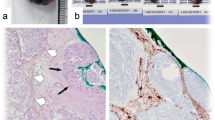

Preoperative radiological imaging was analyzed by a team of two independent and experienced radiologists (AA and PBS). For statistical analyses, tumor location was classified as “skull base” and “non-skull base” location, subsuming convexity, intraventricular, posterior fossa, and parasagittal lesions. According to previous analyses investigating correlations between MRI findings and high-grade histology or progression [1, 29], the following radiological variables were examined (illustrative samples in Fig. 1): Tumor and edema volumes (VT and VE) were calculated according to the formula for a spheroid V = 4/3 × π × r1 × r2 × r3 (“r” is the tumor radius at the site of its largest extension in axial (r1), coronal (r2), and sagittal (r3) planes [1, 8]. Edema volume was finally calculated by subtraction of the tumor from the edema volume. Disruption of the arachnoid layer was analyzed on T2-weighted imaging and diagnosed in case of an indistinct tumor border and/or lack of a cerebrospinal fluid cleft at the brain/meningioma surface. Contrast enhancement of the tumor was investigated on T1-weigthed gadolinium-enhanced images and diagnosed as either heterogeneous or homogenous. Similarly, capsular contrast enhancement was identified on T1-weigthed gadolinium-enhanced images and described as present, if more than half of the tumor surface enhanced, otherwise as absent. Intensity of the tumor was analyzed on T2-weighted images and classified as hyper-, iso-, or hypointense compared to the gray matter, while calcifications were classified as present or absent. Contrast enhancement of the tumor capsule was dichotomously evaluated as absent or present on gadolinium-enhanced T1-weighted imaging. The tumor shape was classified as regular or irregular, e.g., in terms of mushroom-like growth. All variables were thoroughly radiologically analyzed and classified based on the individual evaluation of the two radiologists. Disagreement was solved by discussion.

Illustrative samples of the analyzed radiological variables. In a, axial T2-weighted MRI shows a thin cerebrospinal fluid cleft (solid arrow, intact arachnoid layer) at the surface between the brain and the T2-hyperintense, regular shaped tumor with some calcifications (dashed arrow) at its origin at the sphenoid ridge. In b, sagittal T1-weighted contrast-enhanced imaging shows an irregularly, mushroom-like shaped lesion (solid arrow) with heterogeneous gadolinium enhancement of the tumor, an enhancing tumor capsule (dashed arrow) and a moderate perifocal edema (asterisk). In c, axial T2-weighted MRI depicts the lack of a cerebrospinal fluid cleft at the brain/tumor surface, indicating a disruption of the arachnoid layer